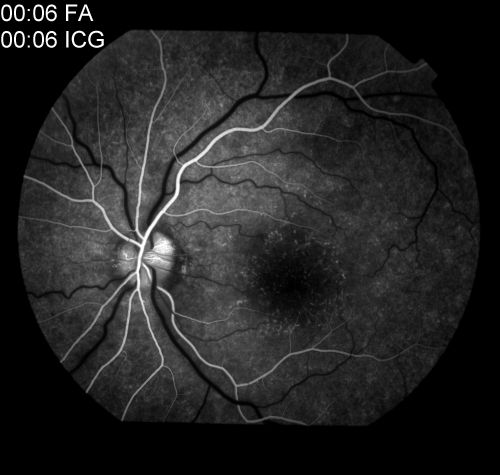

MEWDS

Multiple evanescent white dot syndrome (MEWDS) with classic "wreath pattern" and early optic nerve hyper fluorescence during the arterial phase of the fluorescein angiogram.